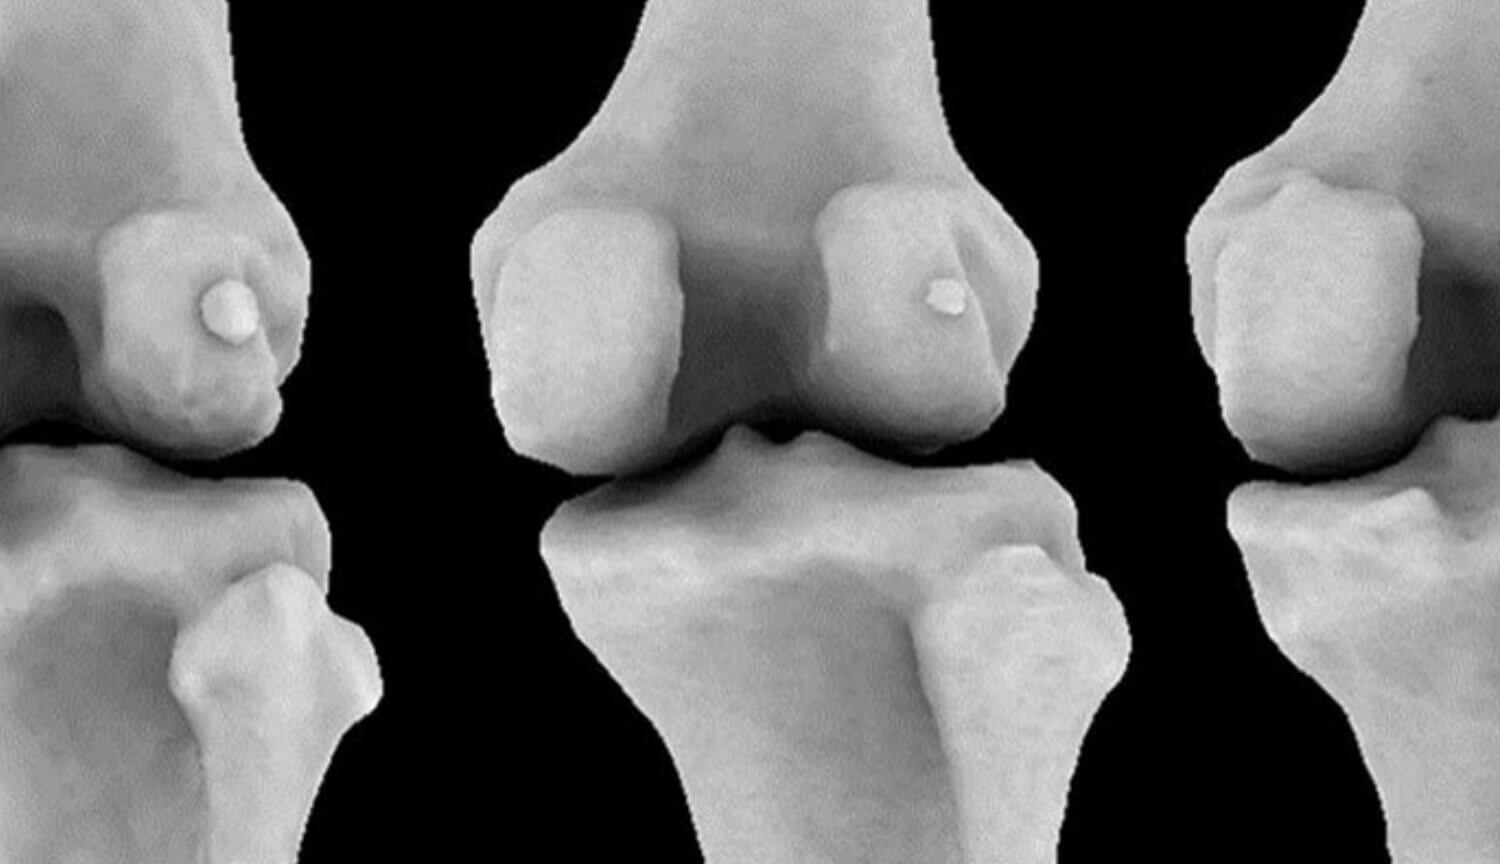

В ходе эволюции некоторые части человеческого тела стали бесполезными, и даже начали исчезать. Яркий пример — кость под названием фабелла, располагавшаяся сзади колена и имевшая крайне маленький размер. У современных людей она встречается крайне редко, поэтому ученые даже не интересовались ее функцией — известно только то, что она часто имеется у людей, страдающих остеоартритом. За последние сотню лет она, по какой-то причине, начала чаще появляться в скелетах людей, из-за чего возникает вопрос — с чем связано ее возвращение?

Открытие было сделано исследователями из Имперского колледжа в Лондоне, изучивших анатомию людей на основе 58 научных работ ученых из разных стран. Выяснилось, что в 1875 году эта небольшая кость встречалась у 17% людей, а к 2018 году ее распространенность увеличилась в 3,5 раза — ее нашли в ногах у 39% жителей Земли.

Она классифицируется как сесамовидная кость — обычно они располагаются в толще сухожилий и примыкают к другим костям. Ученые считают что она, как и другие подобные кости, может служить для уменьшения трения в сухожилиях. При этом, огромное количество людей прекрасно обходится и без нее, поэтому ученые задаются вопросом — с чем связано ее активное возвращение?